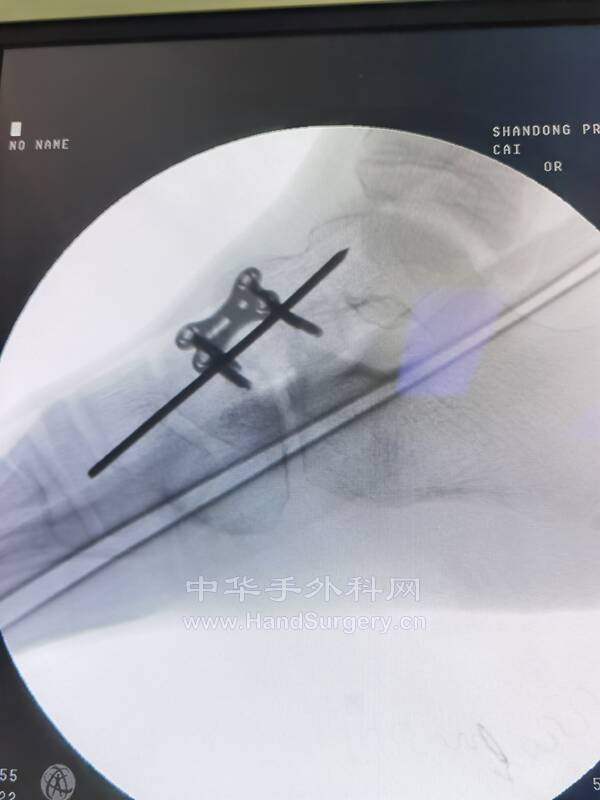

研究等待了一天,结果老师一个术式解决所有问题!还是自己的认识太浅…

IMG_20220806_153529.jpg

IMG_20220806_162343.jpg

IMG_20220806_162530.jpg

mmexport1659877458259.jpg